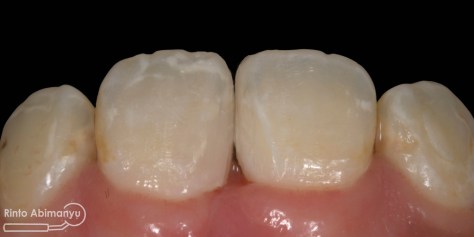

Setalah pengisian usahakan kamar pulpa dibersihkan dari sisa2 siler dan kotoran2 agar bahan adhesive yang kita pakai untuk restorasi dapat melekat maksimal.. Untuk basis saya menggunakan X-tra Base (Voco) kemudian diatasnya memakai komposit Z 350 XT (3M)…

Alhamdulillah perawatan ini tidak ada kendala dan bisa diselesaikan dalam satu kali kunjungan langsung dua gigi… Ronsen sangat penting dalam prosedur perawatan saluran akar, jadi pesan saya adalah “No Xray, No Endo” 🙂